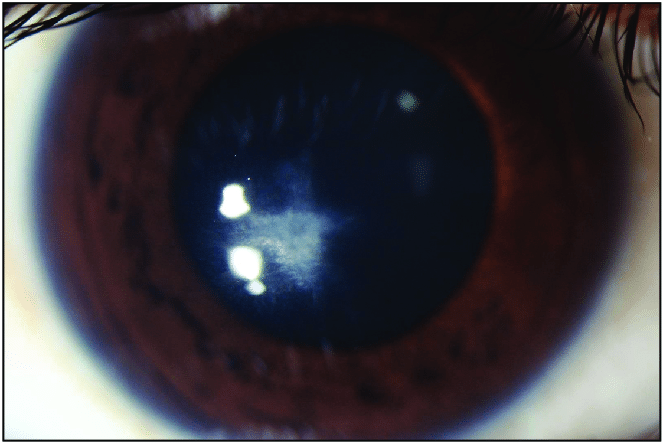

각막수종 Keratoconus Hydrops 라는것은

각막의 Descemet 막 파열로 인해 전방에서부터 수분이 각막기질로 유입되면서 갑작스럽게 각막이 뿌옇게되는 현상을 의미합니다.

데스메막이 늘어나다보니 파열되면서 그 틈을 통해 방수가 기질에 들어가 기질 부종이 생기게되면,

수주 ~ 수개월간 부종이 지속되게되는데,

이후 대부분 서서히 부종은 빠지나, 이때 각막이 부풀었다가 가라앉게 되면서 흉터가 발생하게되며

특히 이때 각막의 앞쪽의 보우만막이 파열되면서 흉터가 자주생깁니다.